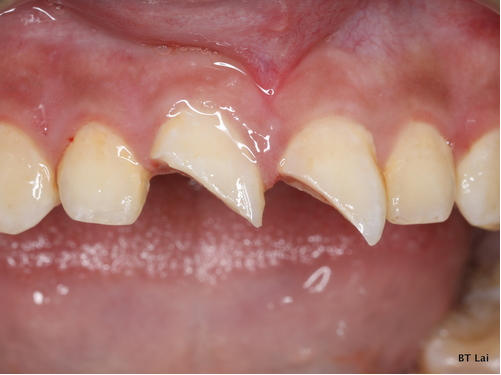

7歲孩童小松是在一年半前不小心把上顎新萌發的恆齒撞斷,經急診醫師會診根管治療科賴博堂主任接手以活髓治療。現在的小松雖然偶爾會因咬到堅硬的食物而使黏上去的斷片掉落,需再重新黏上之外,整顆牙仍保留恆齒成長潛能。

右圖:7歲孩童小松是在一年半前不小心把上顎新萌發的恆齒撞斷,圖為術前照片1。(賴博堂提供)